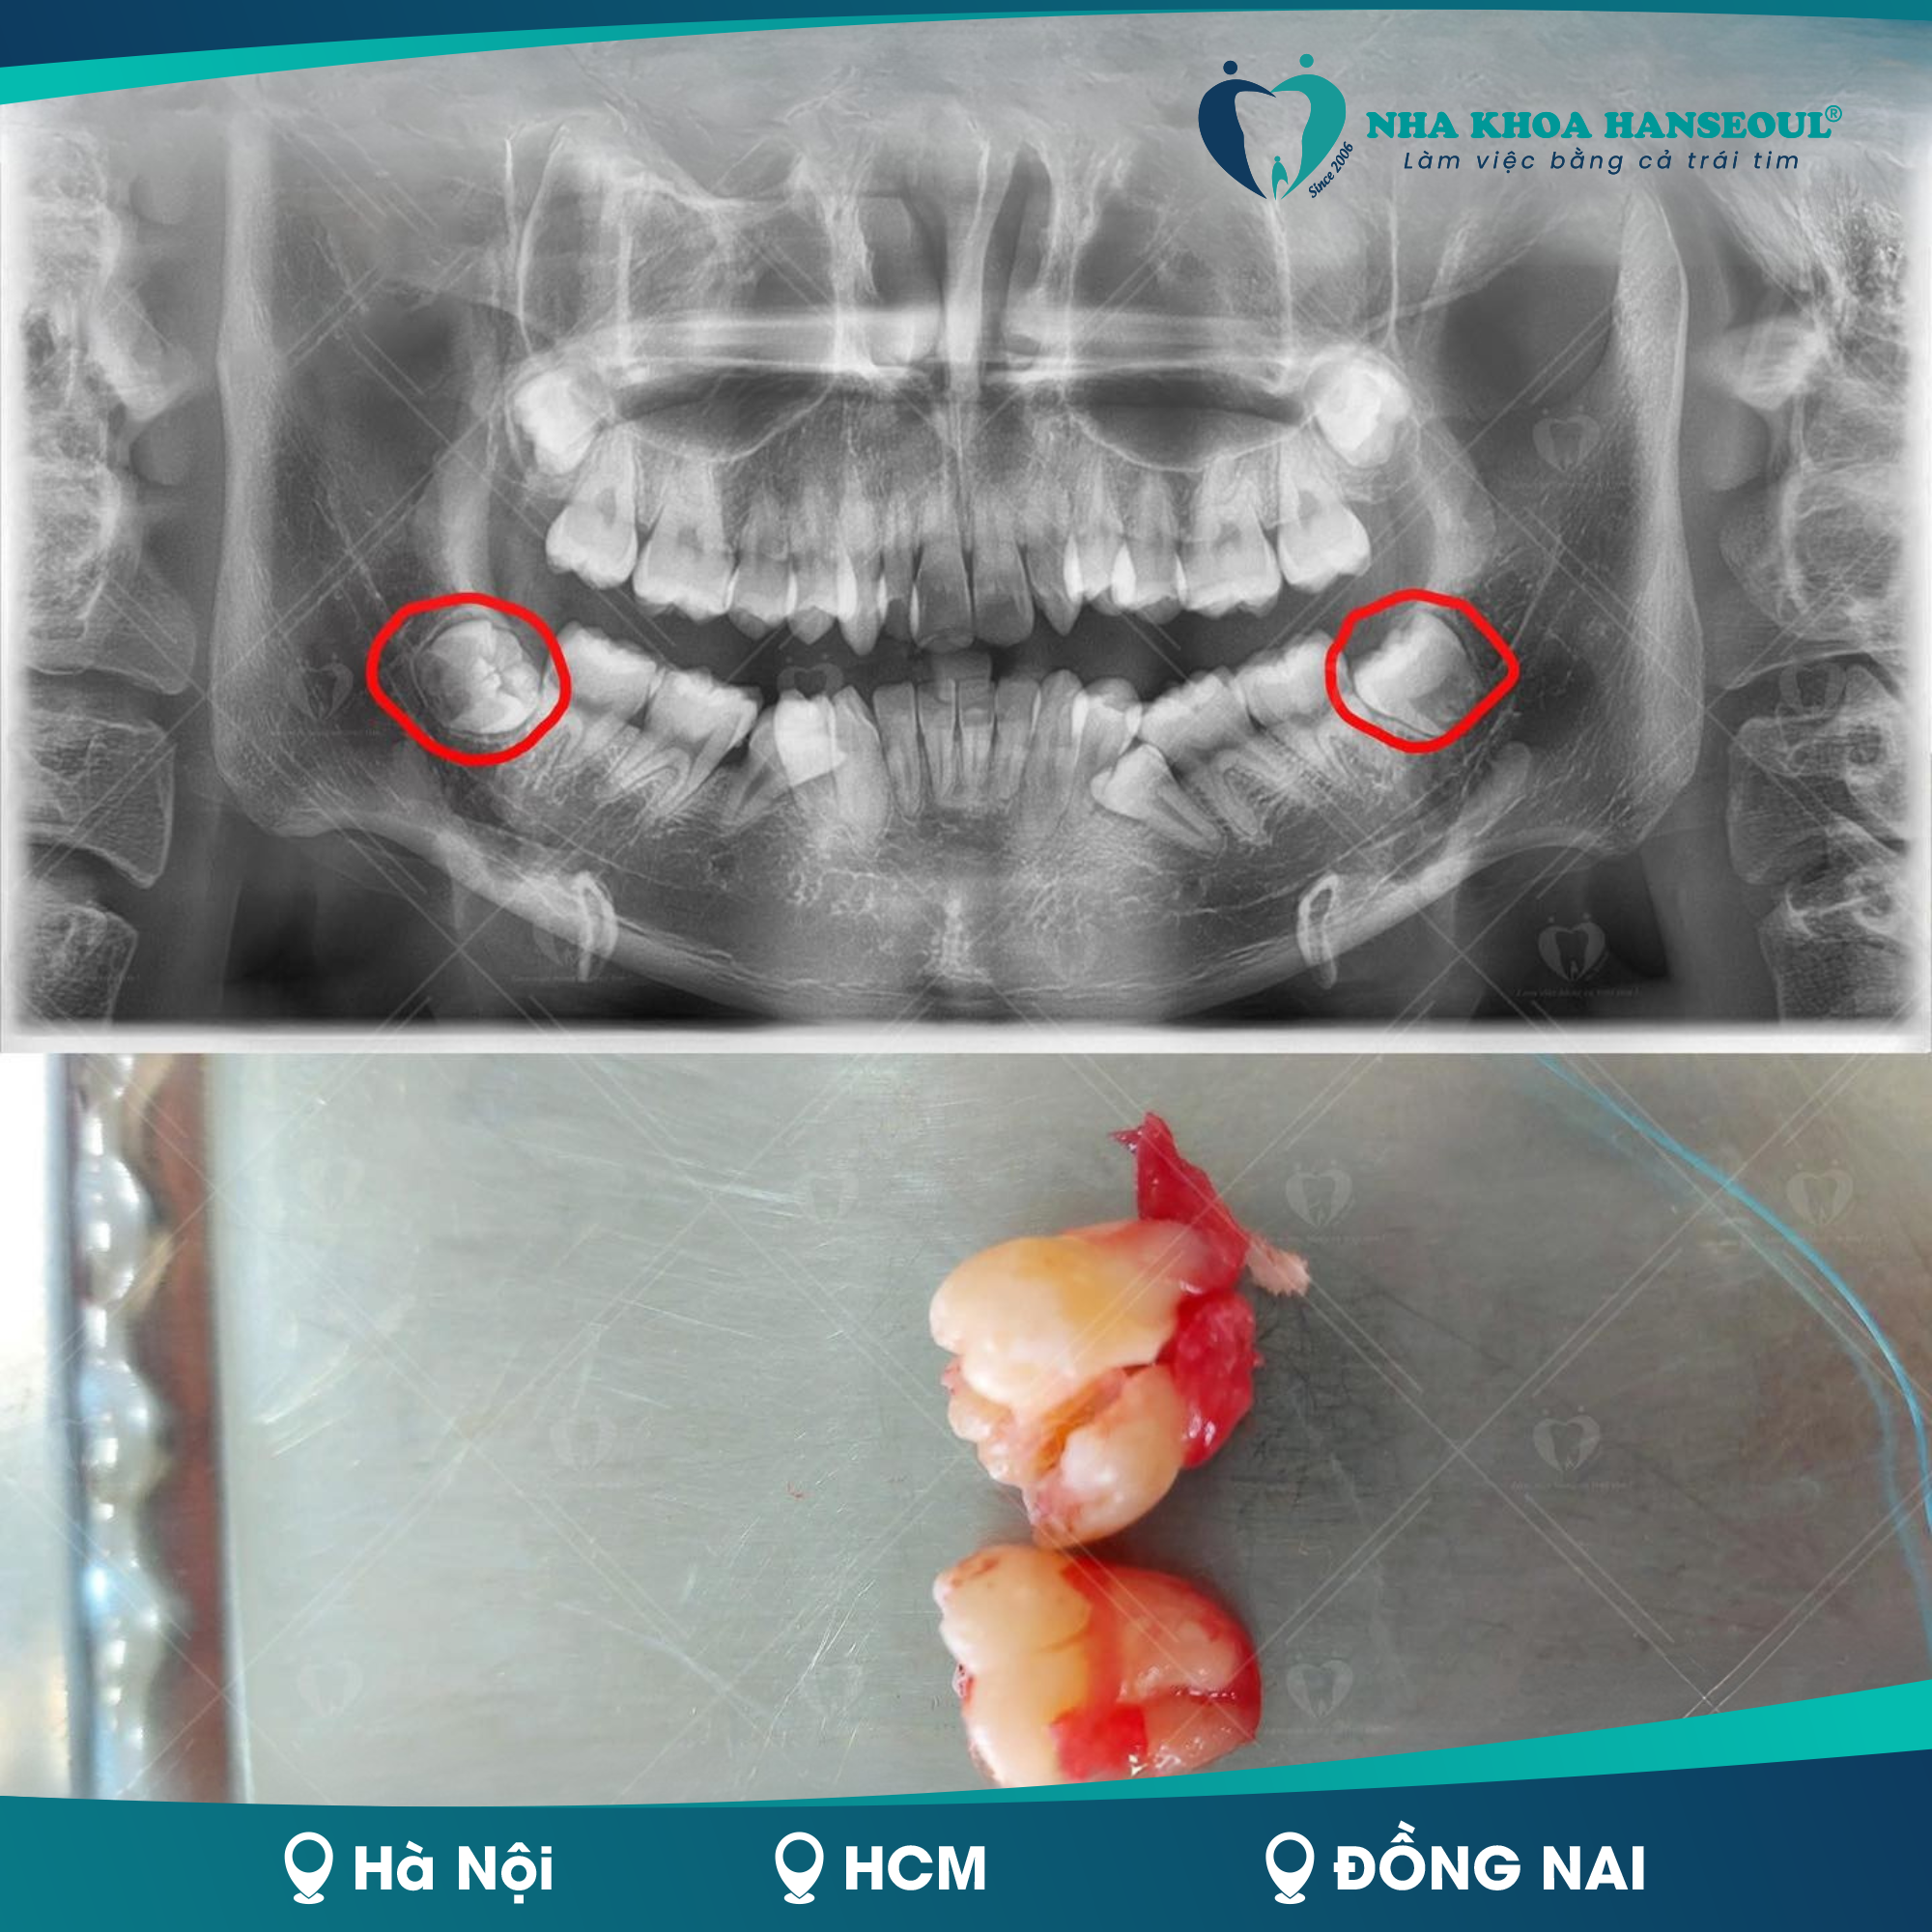

Có nên nhổ răng số 8 khi đang niềng răng?